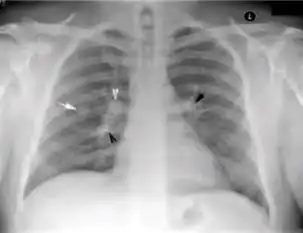

-

Chest X-ray of a person with advanced tuberculosis: Infection in both lungs is marked by white arrow-heads, and the formation of a cavity is marked by black arrows.